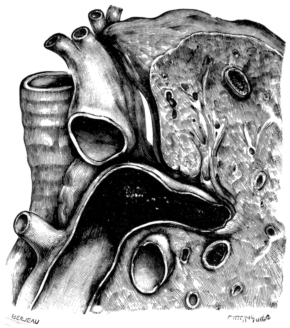

| 25. | The Pulmonary Artery and Adjacent Part of the Lung and Trachea | 103 |

| 274. | Aneurism of the Aorta perforating the Trachea | 542 |